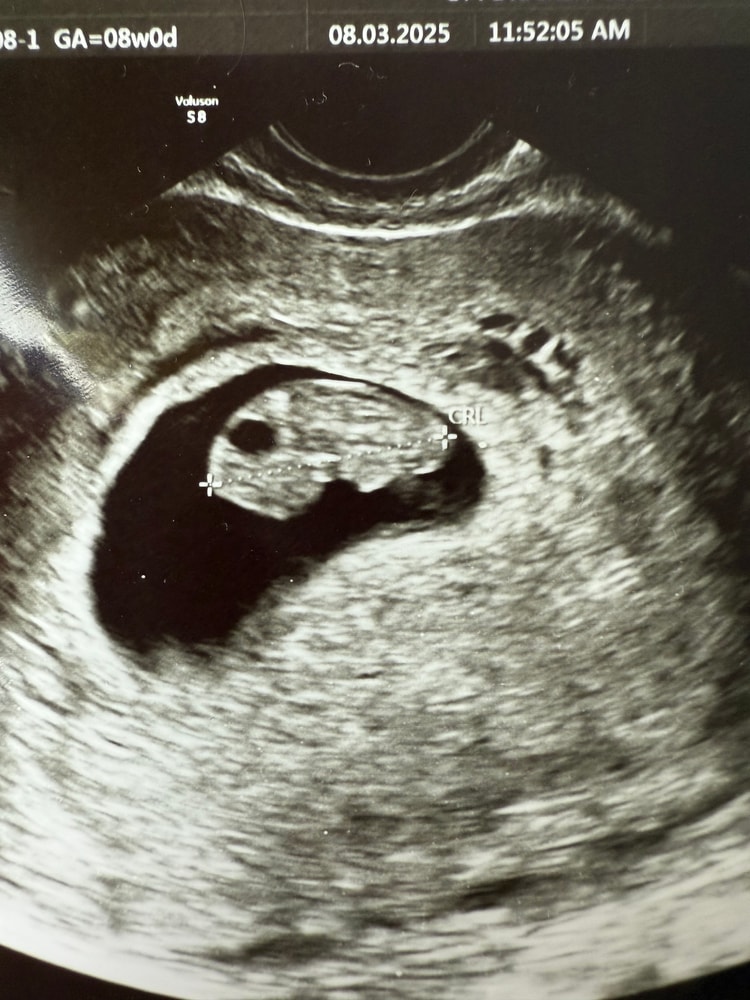

В 6 недель было два ПЯ, в одном был эмбрион с сердцебиением, на трансвагинальном узи обнаружили второе, оно было пустым, врач сказала прийти через неделю, скорее всего второе пя уйдет.

Пришла через неделю, по словам врача оно ушло.

Через неделю я пошла к другому врачу, она увидела гематому рядом с пя, прописала антибиотик, чтобы исключить инфекцию в ней, и прогестерон. На 9 неделе снова было узи, сказала, что гематома вроде как уменьшилась.

Скажите, можно ли не заметить двойню на этом сроке, если она за другим пя прячется, или все-таки сейчас уже точно один ребенок? Как-то меня мысли о двойне не покидают 🙈 особенно смущает мой живот, который не должен вроде еще расти

Добрый день. Срок для установления двойни достаточно большой и показательный. У меня оба раза видели хорошо уже в 8 недель. Смотрели разными датчиками. Даже на плохоньком аппарате.